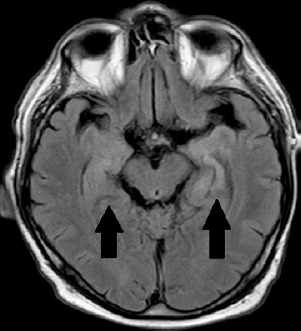

目的:本病例的目的是介绍对新发记忆障碍伴癫痫发作患者进行深入分析的意义。病例描述:我们报告一例61岁男性患者,因不明原因的记忆障碍和癫痫发作而入院。进一步检查显示存在抗lgi1(富含亮氨酸的胶质瘤失活1)抗体。腹腔计算机断层扫描显示胃和脾脏之间有肿块。组织病理学检查确定肿块为胃肠道肿瘤(GIST)。手术切除肿瘤后,症状明显减轻。肿瘤的早期诊断和治疗有助于患者的神经学和肿瘤学预后。评论:副肿瘤神经系统综合征是一种神经系统功能受损的临床症状,不是由局部肿瘤生长或转移引起的。目前公认的这种情况的潜在机制是发生在患者体内的自身免疫反应。作为对肿瘤存在的反应,一种被称为肿瘤神经抗体的抗体被产生,这种抗体随后被用于对抗神经系统细胞上的抗原。据我们所知,这是第一个也是迄今为止唯一一个抗lgi1抗体自身免疫性脑炎作为与GIST相关的神经副肿瘤综合征。

Case description: We present a case of a 61-year-old male patient who was admitted to the hospital due to unexplained memory disorders and seizures. Further examination showed the presence of anti-LGI1 (leucine-rich glioma-inactivated 1) antibodies. Computed tomography of the abdominal cavity revealed a mass located between the stomach and the spleen. Histopathological examination identified the mass as a gastrointestinal tumour (GIST). After the surgical removal of the tumour the symptoms were significantly reduced. The early diagnosis and treatment of the tumour contributed to favourable neurological and oncological outcomes for the patient.